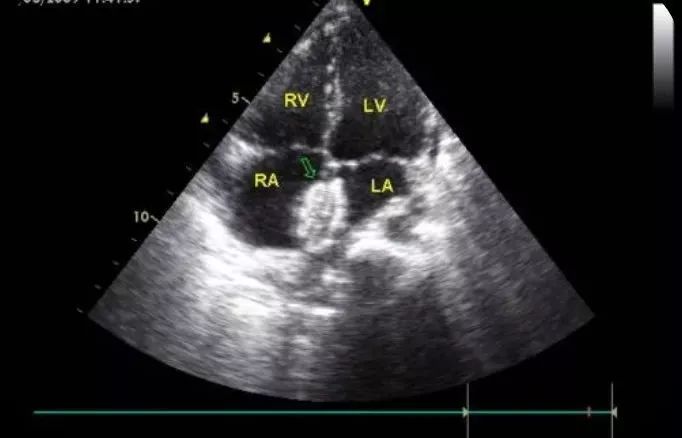

华法林嵴(coumadin ridge) [病例帖]

华法林嵴or三房心再认识华法林嵴